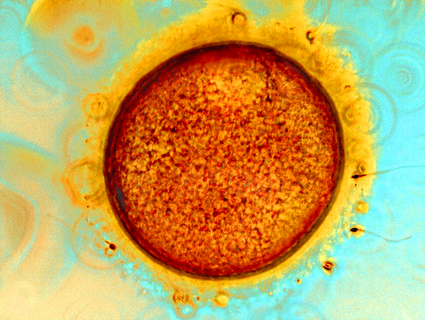

A group of doctors also came out against the measure in a press conference at the state capitol. Dr. Randall Hines, a Flowood, Mississippi-based OB/GYN who specializes in infertility treatments, tells Mother Jones that the testimonials on Facebook and other social media tools from women were another key factor in the measure’s defeat. “The number of people who themselves, a family member, or a close friend has experienced infertility…we’re talking about a big chunk of the population,” Hines says. “I think that was overwhelmingly what got this thing defeated.”

Hines also cited the involvement of grassroots parents groups like Parents Against MS 26, an effort started by Atlee Breland, a mother of three who dealt with infertility. “The way I built my family was under threat,” Breland said. “I couldn’t let that go.” She launched a website with the stories of women who had undergone fertility treatments, been through rapes, or suffered traumatic miscarriages. Many of the women described themselves as firmly pro-life, but concerned about the broader reach of measure.